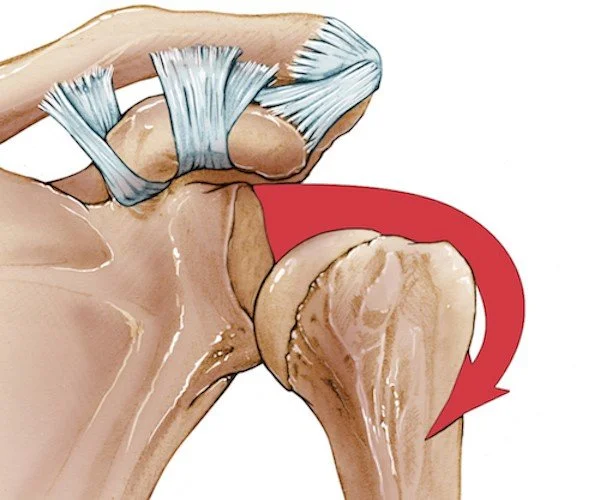

Shoulder instability is when the head of the upper arm bone (humeral head) is forced out of the shoulder socket (glenoid fossa). There are three types of shoulder instability: Anterior, Posterior, and Multidirectional.

Athletes have a 95% chance of obtaining Anterior Instability, making it the most common type of shoulder instability. In an anterior unstable shoulder, the humeral head is forced to the front side of the body (anterior side). This is caused by excessively moving your arm laterally (abduction) and rotating your elbows forward (external rotation). An example is throwing a ball.

There is a 30-40% chance of getting the bankart lesion and/or the hill sachs lesion when experiencing an anterior unstable shoulder. Both lesions are complementary, as one causes the other to happen. A Bankart lesion happens when the connective tissues (on the anterior side) that hold the ball and socket together are damaged. The Hill-Sachs Lesion is when the ball of the humeral head gets fractured/ slight indentation caused by the compression of the anterior side of the socket.

Lateral view of the glenohumeral (socket-to-ball) joint; right shoulder